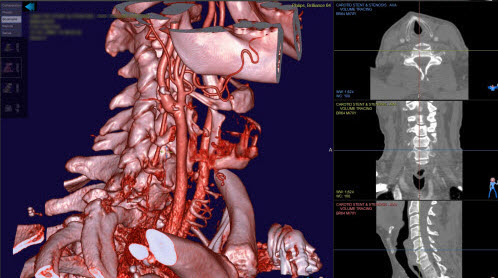

3D view